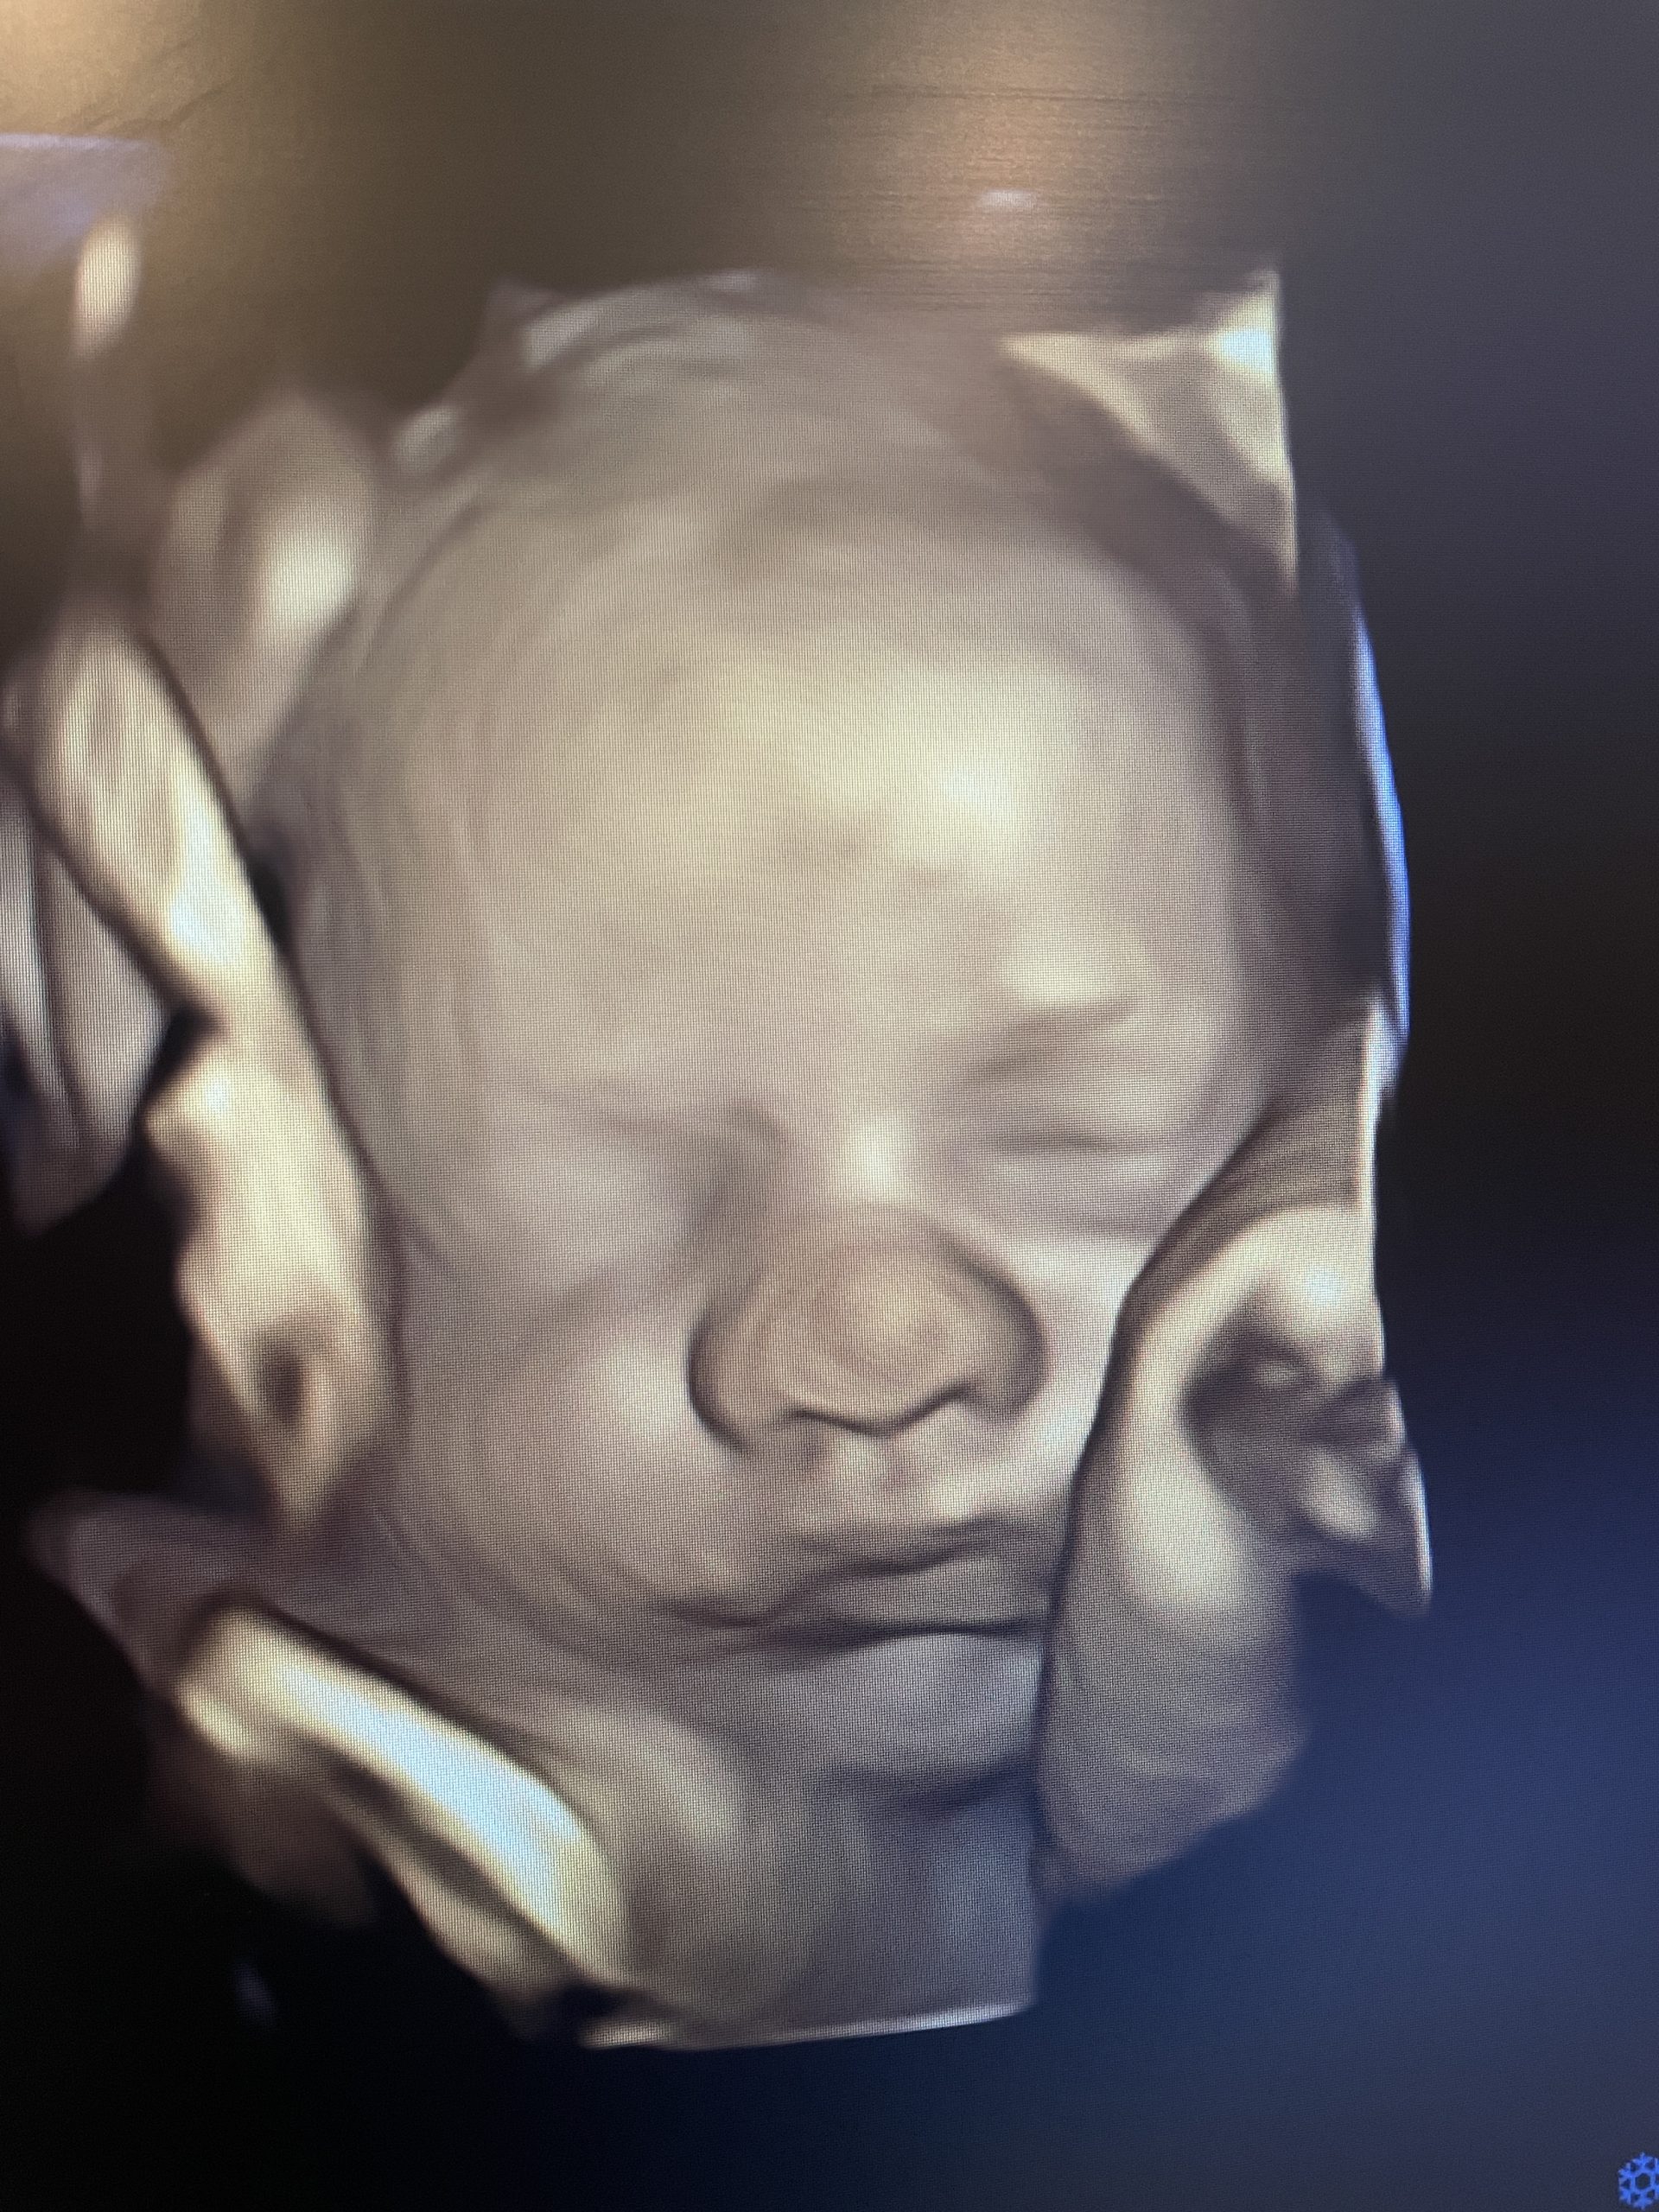

Control prenatal con ultrasonido 4D

Cada consulta incluye valoración médica completa y seguimiento estructurado de tu embarazo.

El ultrasonido 4D de alta definición permite:

• Evaluar el crecimiento y bienestar de tu bebé

• Detectar oportunamente cualquier alteración

• Dar seguimiento preciso en cada trimestre

• Fortalecer el vínculo emocional con tu bebé

• Recibir información clara y visual en cada cita reduce la incertidumbre y te permite tomar decisiones informadas.